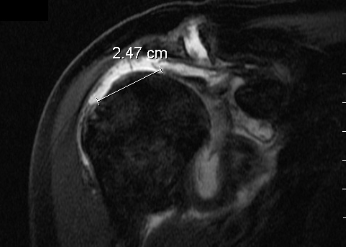

O diagnóstico pode ser realizado através de Ecografia e/ou Ressonância Magnética. O RX deve ser realizado para avaliar o estado da articulação, pois este pode influenciar na escolha do tratamento. O RX mostra as alterações ósseas e dá sinais indiretos de lesão dos tendões.

A Ressonância Magnética mostra a localização da rotura, a dimensão, a qualidade do tendão rompido, sendo por isso o exame mais importante numa suspeita de rotura da coifa dos rotadores. (Fig. 4)